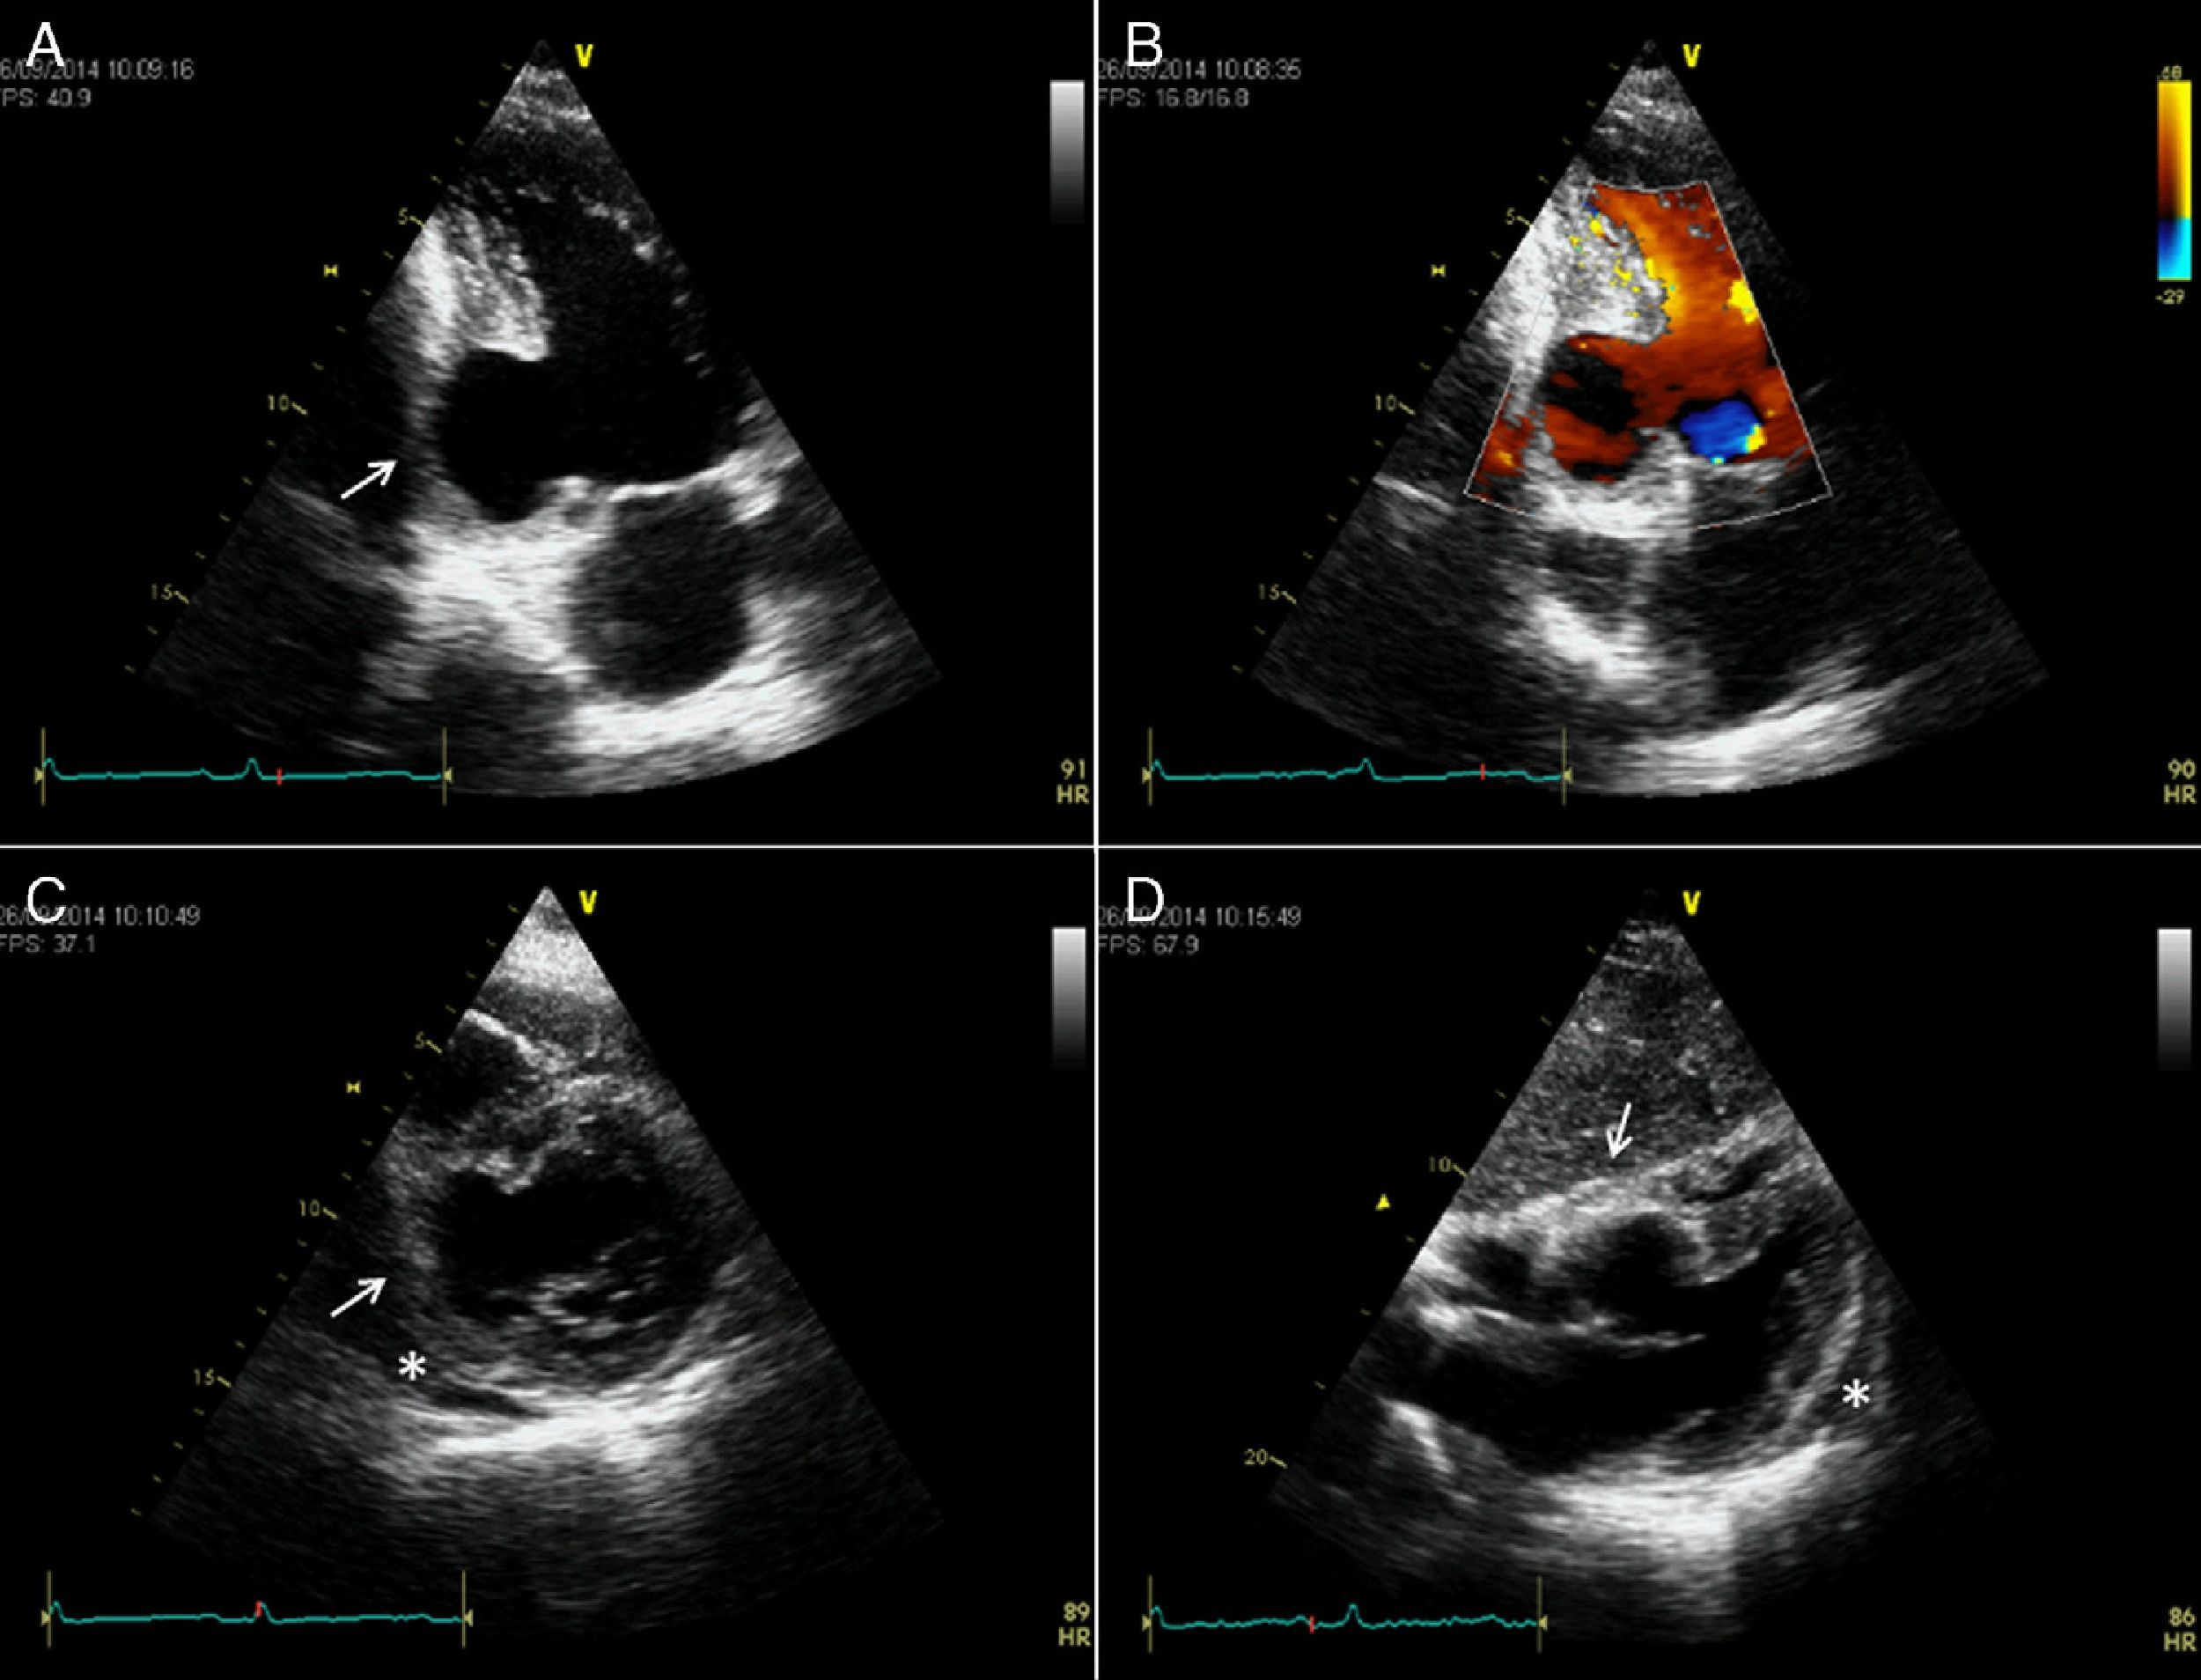

True cardiac aneurysm

What is seen in the 2D image?

Pseudoaneurysm